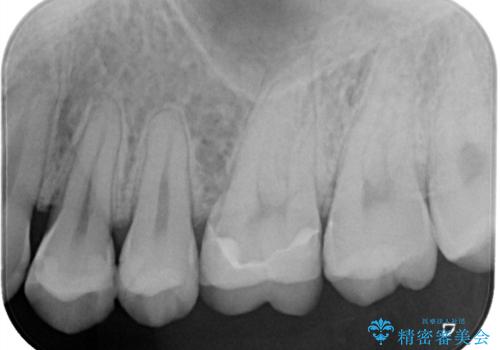

- 冷たいものがしみるとご相談に来られた患者様です。一見、外からではわかりづらい部分に深めの虫歯を認めたため、神経保護の意味合いも兼ねて即日にてセラミック修復を行いました。術後も経過良好です。